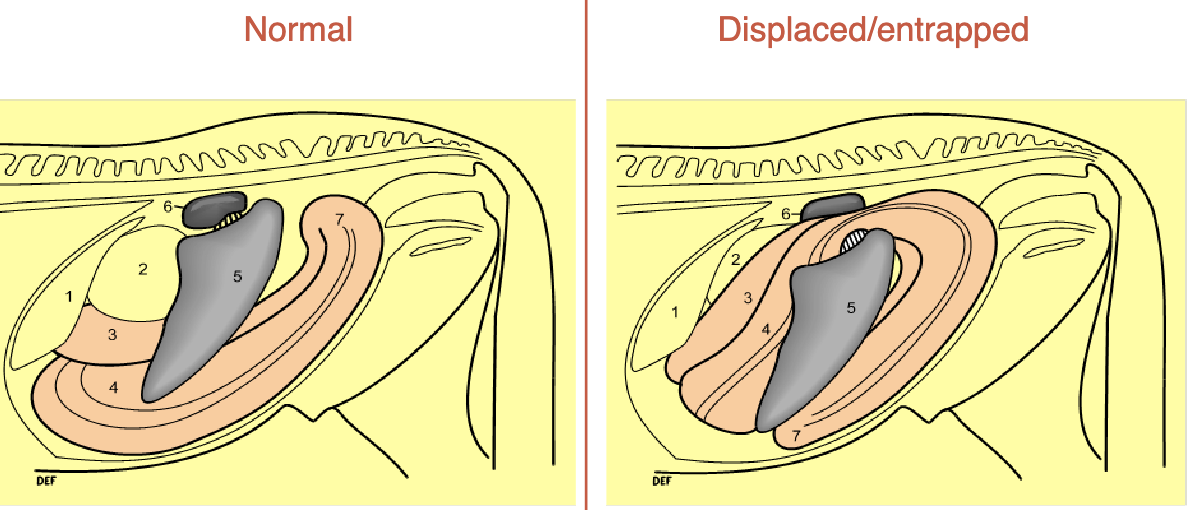

pathway for normal abdomen anatomy

esophagus→stomach→duodenum→jejunum→ileum→cecum(R side, blind ending sac)→right ventral colon→sternal flexure→left ventral colon→pelvic flexure→left dorsal colon→diaphragmatic flexure→right dorsal colon→transverse colon→small colon→rectum

difference btwn dorsal and ventral colons

dorsal= smooth

ventral= has sacculations (bumpy)